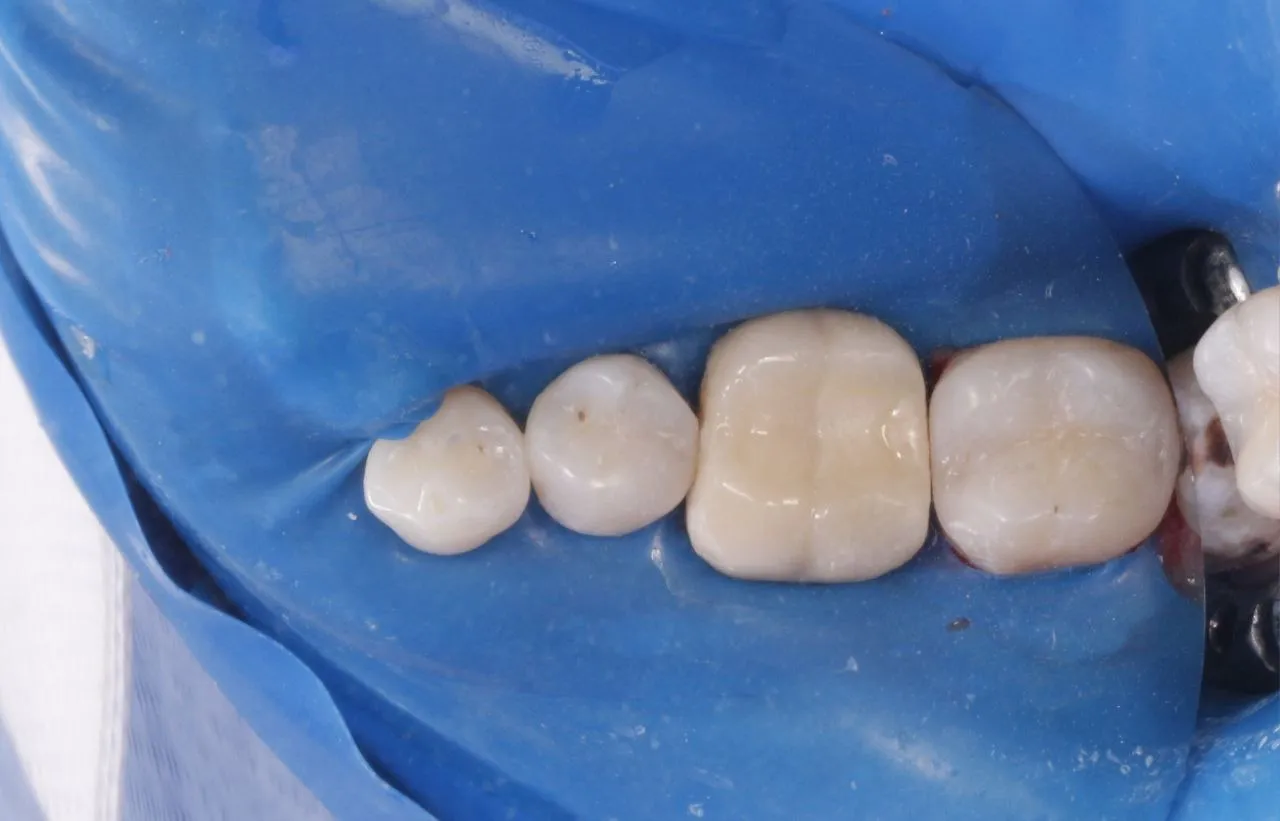

Лікування глибокого вторинного карієса зубів 17 та 16